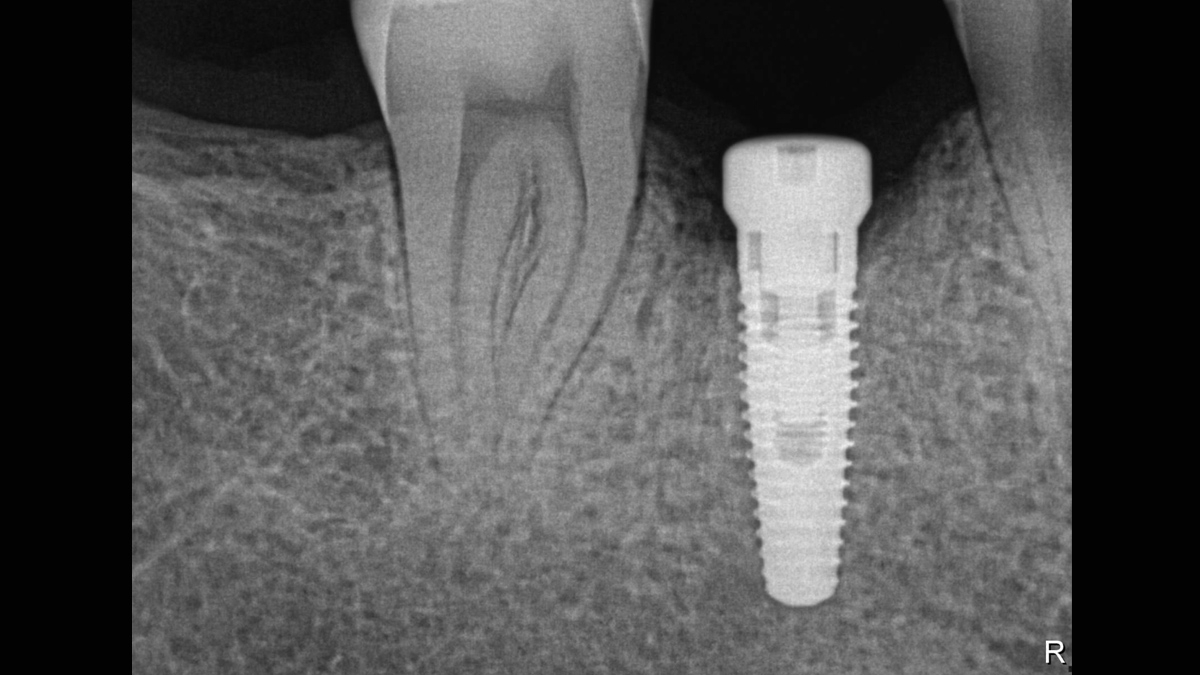

Los sensores intraorales de Dentsply Sirona proporcionan calidad de imagen de vanguardia que apoya el diagnóstico preciso del tratamiento y visión clara de la situación clínica. Respaldado por elecciones expansivas del sistema, mejora de filtro de imagen y servicio de vanguardia y personal de apoyo, los sensores intraorales Xios ofrecen varias posibilidades para su consultorio - brindándole beneficio a usted y sus pacientes.